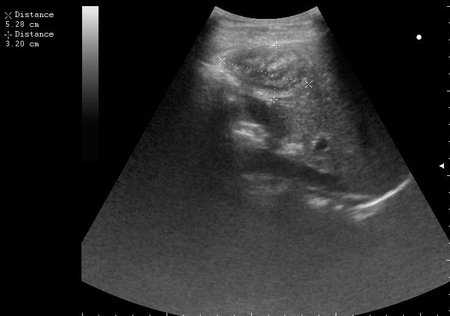

17-летняя девушка с множественными поражениями печени

2.JPG

3.JPG

4.JPG